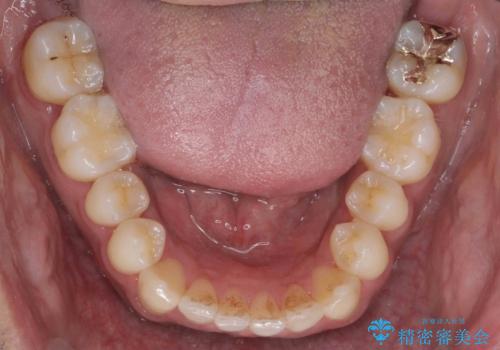

上はワイヤー部分矯正、下はインビザラインの部分矯正コースを行いました。

インビザラインだけでも治療は可能ではあると思いますが、ライトパッケージでは難しいと思います。

また、入れ替えを行う間左上の前歯だけで咬まなくてはならない状況になるため、マウスピース矯正単独で行うと時間がかかり、最悪神経が失活することもありますのでワイヤーがお勧めです。